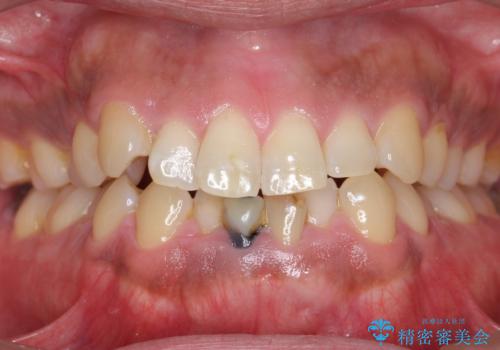

- 下の前歯の色が気になることを主訴に来院された患者様です。

下の前歯は金属の土台により黒くなり、隣の歯も神経が死んで暗く変色していました。

神経が死んでいる歯の根管治療を行った後、セラミッククラウンによる補綴治療を行いました。

※右下1の再根管治療もおすすめしましたがご希望されませんでした。

※下顎前歯部の叢生について矯正も提案致しましたが、ご希望されませんでした。